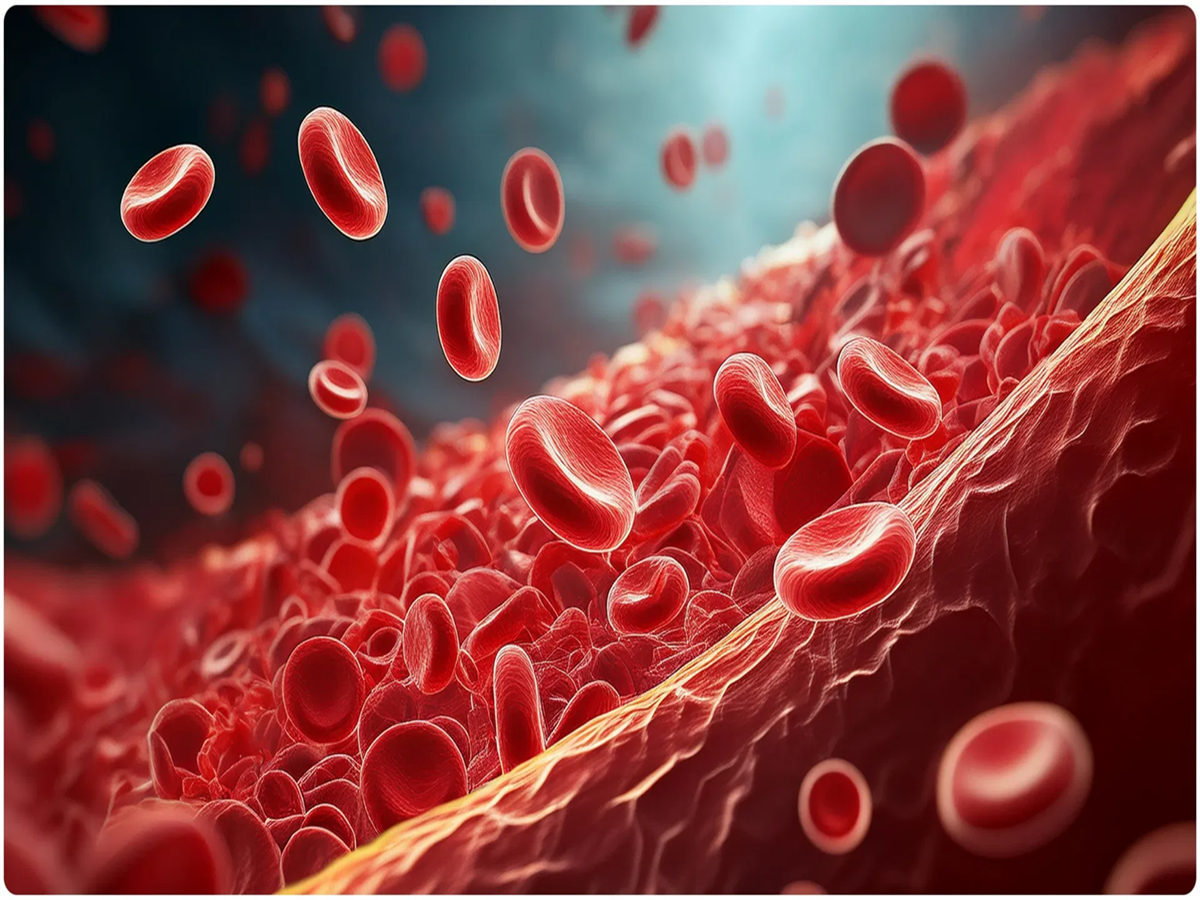

Immediate Effects on the Heart and Blood Vessels

According to a study, the blood vessels in your body begin to be affected within just 30 minutes of exposure to passive smoking. Nicotine and carbon monoxide in smoke damage the inner lining of the arteries, causing them to harden. This condition can cause irregular heartbeat and, in the long term, increase the risk of heart attack and coronary heart disease by 25-30%.